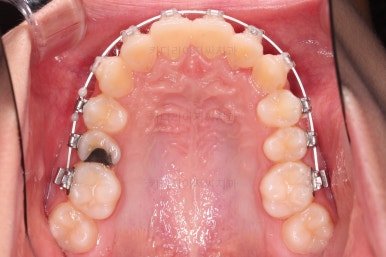

다양한 테크닉적으로 조금 더 여러 가지를 개선하고 부산교정치료 마무리를 합니다.

덧니도 개선되었고 가지런한 느낌도 좋네요.

교합도 좋고, 평행하지 않던 느낌도 많이 좋아졌습니다.

전후 사진을 보여드리겠습니다.

많은 부분이 좋아졌고요.

웃을 때 기울어져 보이던 치열의 모습도 좋아졌습니다.